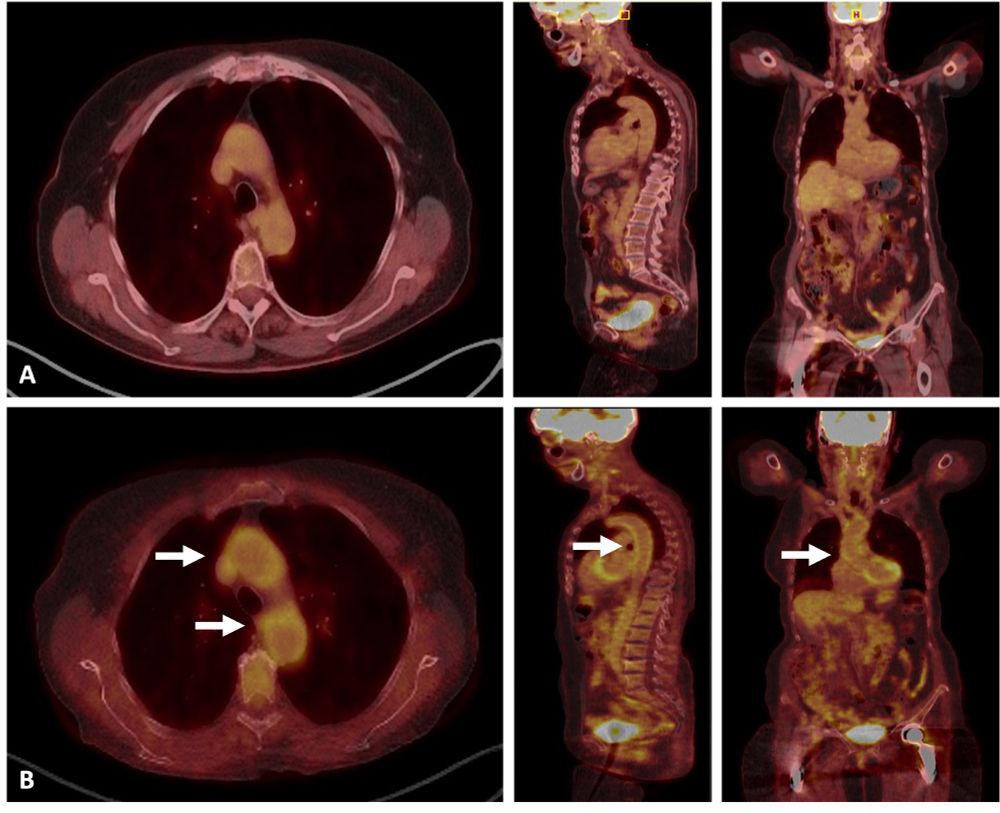

Large-vessel vasculitis relapse in an 83-year-old woman with biopsy-proven giant cell arteritis characterized by 3-week history of headache, scalp tenderness, jaw claudication, and constitutional symptoms.

Suggested management algorithm for patients with GCA relapses